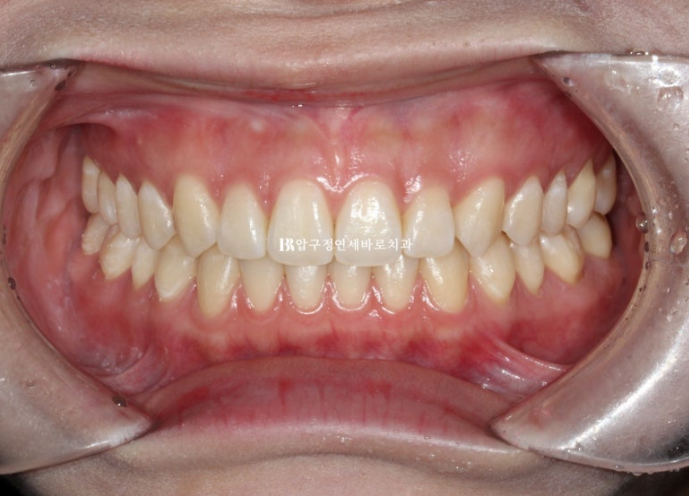

24.11

물샐틈 없는 교합이 보입니다.

마지막 1-2주는 장치를 앞니쪽만 남기고 어금니쪽을 잘라내어 자연스러운 교합안정화를 도모했습니다.

인비절라인은 교합이 안 좋게 끝난다는 편견을 깨기 위해 이렇게 포스팅을 작성합니다.